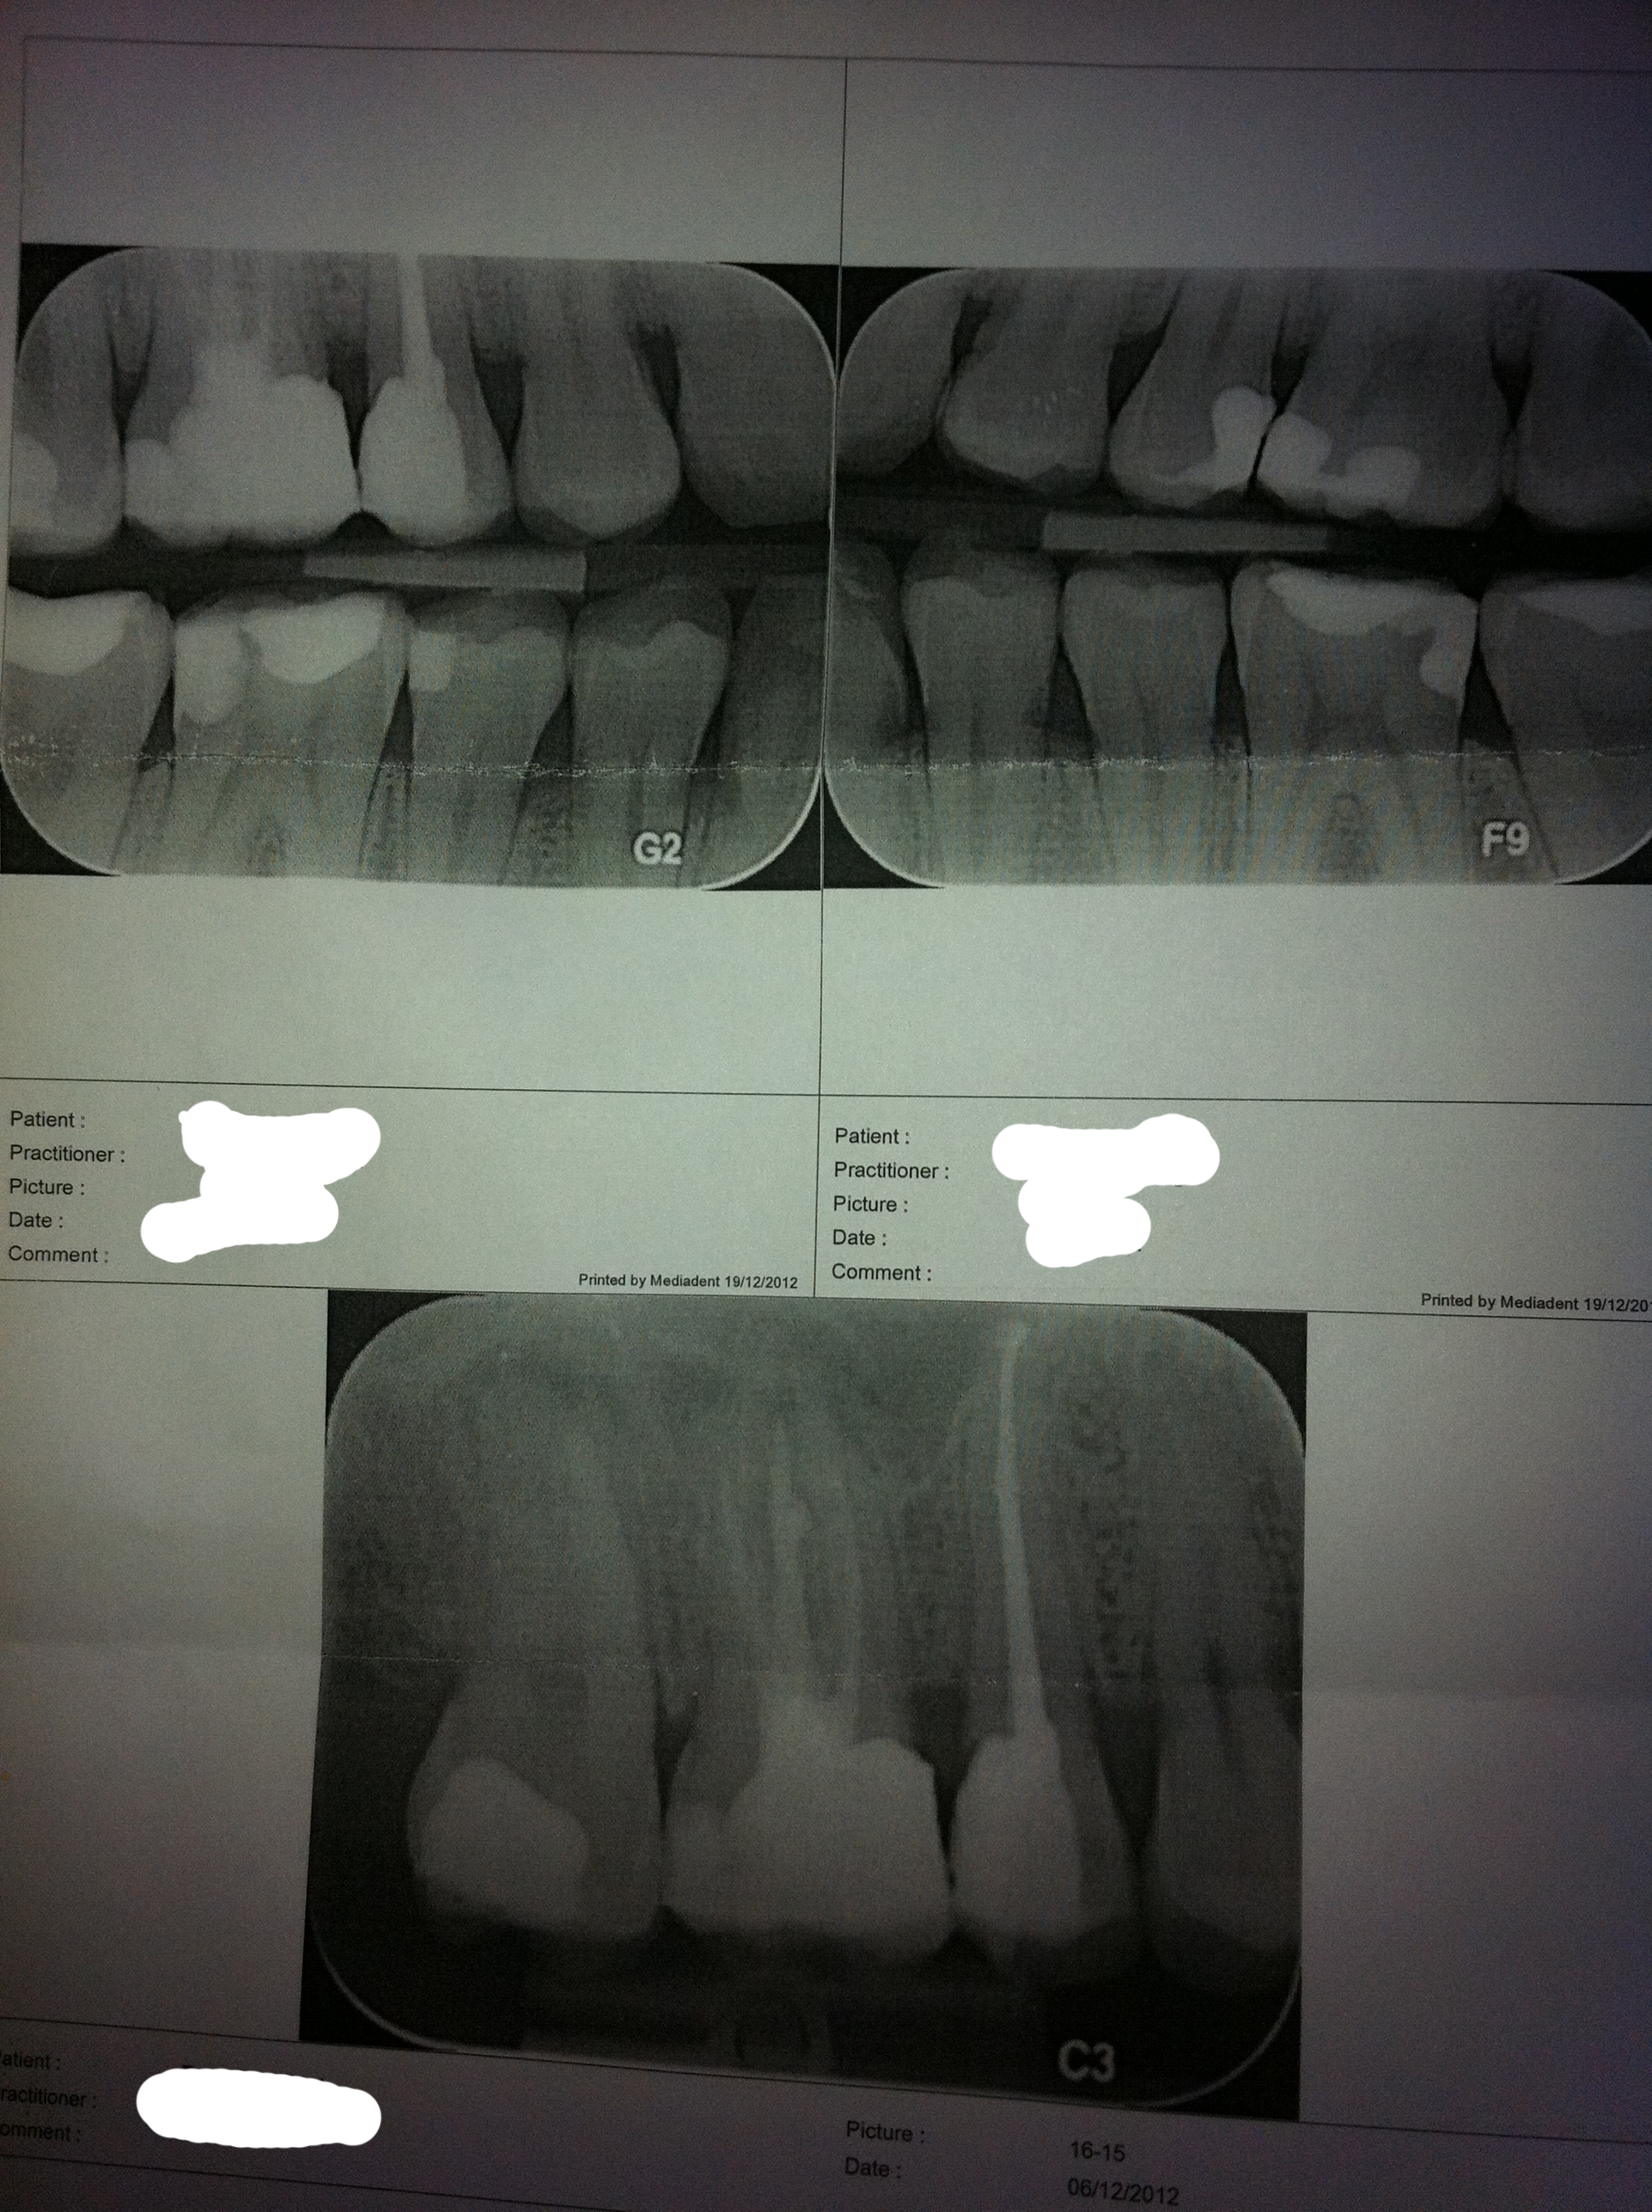

Ik heb heel vaak/snel last van ontstoken tandvlees op 1 specifieke plek. Het is bij een kies waar een behoorlijk grote vulling inzit. Zie de bijgevoegde afbeelding. Op de onderste röntgenfoto betreft het in ieder geval het tandvlees rechts van de tand met de grote vulling (middelste). Is op basis van deze röntgenfoto's wat raars te zien qua ontsteking, kaakbot/ paradontis of iets dergelijks?

Dit is waarschijnlijk geen parodontitis, maar een wortelpuntontsteking. Bij de laatste kies een onbehandelde en bij de middelste een behandelde. De kanalen lijken niet helemaal tot de punt gevuld. Heel veel weet ik hier niet van. Hopelijk reageerd er nog een tandarts.

Ja, de vulling in de grote kies staat 'over' (t randje van de vuling steekt een beetje uit) en bij de kleine kies ernaast staat de vullin 'onder' (vulling haalt de rand van de kies niet). Ik denk dat dat de plakretentie wel bevorderd en de reiniging niet echt, waardoor irritatie van het tandvlees zeker wel op de loer ligt.

Voor wat betreft de discussie over de wkb's, een korte wkb wil niet zeggen dat er een ontsteking aan de wortelpunt is per sé. Op basis van een foto van een geprinte röntgenfoto met half overgeprojecteerde sinus zou ik die diagnose hier niet zo snel voor mijn rekening nemen. Daarbij weten we niet wanneer de solo gemaakt is, en of de mogelijke laesie kleiner is geworden ten opzichte van de eindfoto. En stel dat er een ontstekinkje is....is dat in dit geval wel de oorzaak van de klachten? Gezien de duidelijke omschrijving van de klacht lijkt het mij van niet....en zal dus het op dit moment herbehandelen met als doel het verhelpen van deze klacht waarschijnlijk geen zoden aan de dijk zetten.

Als de klacht uit het tandvlees komt (en daar lijkt het gezien het verhaal sterk op) zou ik een nette kroon op de kleine kies (nette endo, geen ap, grote onderstaande vulling) overwegen en bijwerken van de vullingrand van de grote kies. Daarmee doe je fundamenteel iets aan de randaansluitingen/contactpunten en hou je alle opties open voor de grote kies.